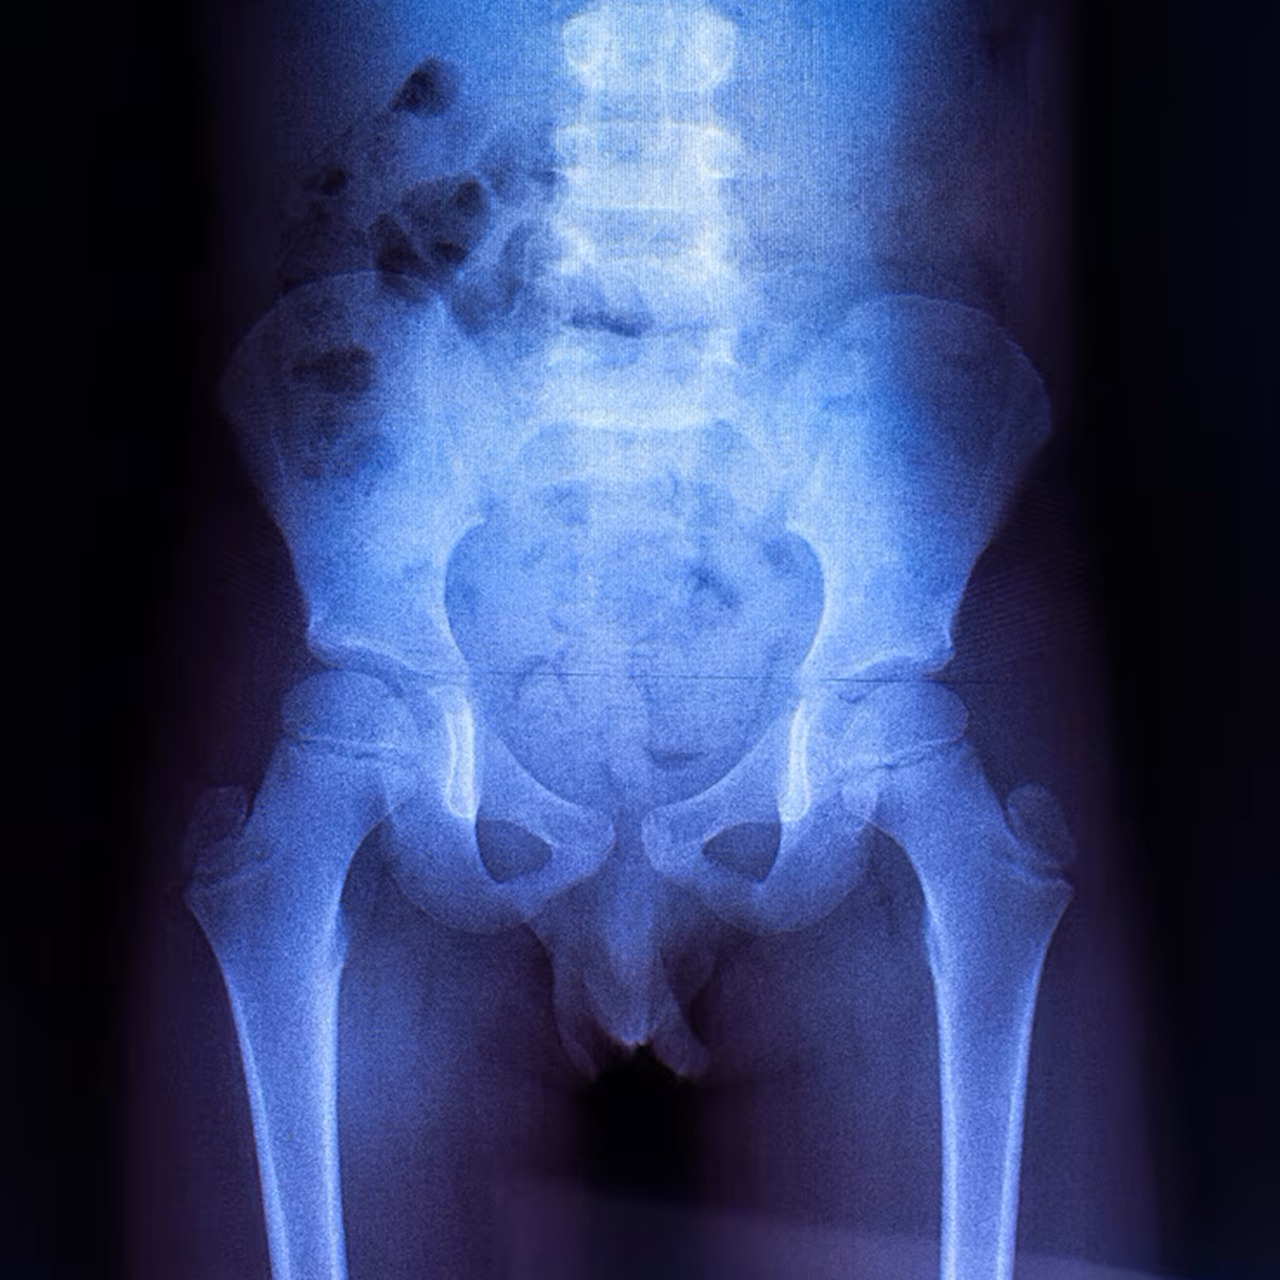

Pelvis X-ray is an imaging test that captures the bones of the pelvic region. It helps detect fractures, arthritis, or structural abnormalities.

Hip X-ray is an imaging test that shows the bones of the hip joint. It helps detect fractures, arthritis, and joint abnormalities.